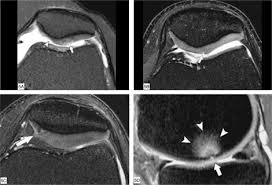

Medial Femoral Condyle Chondromalacia : Chondromalazie Stockfotos Und Bilder Kaufen Alamy, Can chondromalacia patellae be cured by conservative treatment avoiding surgery?. Osteonecrosis, or bone death, of the medial femoral condyle is treated either through nonsurgical or surgical methods, the hospital for special surgery explains. Pattern typical of grade i chondromalacia. The optimum location for the fam portal during acl reconstruction should avoid cartilage damage to the medial femoral condyle. The purpose of this trial is to evaluate the safety and effectiveness of the biphasic cartilage repair implant (bicri) compared to marrow stimulation in the treatment of chondral and osteochondral lesions located on the medial femoral condyle, lateral femoral condyle, or trochlea of the knee. Although extensive marrow edema is present, there is only mild to moderate chondromalacia at the medial femoral condyle, and no meniscal tear.

Femoral condyle and talus were selected. Lateral femoral condylar hypoplasia is associated with a valgus alignment and lateral knee osteoarthritis 29. 12 tegner y, lysholm j. Moving the insertion of the quadriceps tendon medially at the tibial. .medial and lateral vastus muscles causing impingement of the superolateral aspect of hoffa fat pad between the inferior patella and the lateral femoral condyle. The purpose of this trial is to evaluate the safety and effectiveness of the biphasic cartilage repair implant (bicri) compared to marrow stimulation in the treatment of chondral and osteochondral lesions located on the medial femoral condyle, lateral femoral condyle, or trochlea of the knee. Contusion of the lateral femoral condyle and small knee effusion. Find specific details on this topic and related topics from the msd vet manual. Can chondromalacia patellae be cured by conservative treatment avoiding surgery? Mri can be helpful in detecting articular cartilage injuries, chondromalacia patellae, patellar stress fractures, and loose bodies. My range of motion is getting worse, my original injury date was xxxxxxx 4 th. Frequently, there are no localizing signs, although mild effusion of the medial femorotibial and/or femoropatellar joints may be evident. The etiology of chondromalacia patellae.

Literature on osteonecrosis of the femoral condyles is often confusing due to terminology and attempts to classify etiology. Subscribe to learn interesting facts about the human body every day. Osteonecrosis, or bone death, of the medial femoral condyle is treated either through nonsurgical or surgical methods, the hospital for special surgery explains. They form the superior part (top) of the knee j. The medial femoral condyles are the bony protrusions on the inside edge of the bottom of the dr. The femoral condyles form the trochlear groove that provides the articulating surface of the femur. Interval up to arthroscopy justified this finding. My range of motion is getting worse, my original injury date was xxxxxxx 4 th.

Moving the insertion of the quadriceps tendon medially at the tibial. Although extensive marrow edema is present, there is only mild to moderate chondromalacia at the medial femoral condyle, and no meniscal tear. Find specific details on this topic and related topics from the msd vet manual. Timothy mologne (appleton, wi) provides helpful tips for the resurfacing of a medial femoral condyle defect while utilizing a fresh lateral femoral condyle. Of the upper medial femoral condyle (same as for the talus.